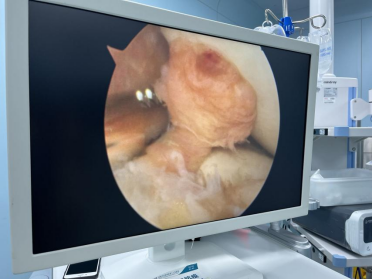

镜下见前交叉韧带完全断裂